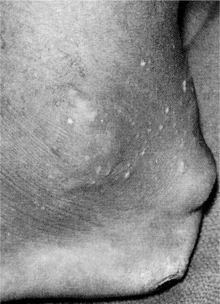

Cutaneous.: The visible rheumatoid nodule is a characteristic skin finding in RA, occurring in approximately 25% of all cases. These granulomatous lesions usually occur in areas of repeated mechanical pressure, such as over the extensor surface of the elbow, Achilles tendon, and extensor surface of the fingers (Fig. 27-13). Nodules are usually asymptomatic, but they can become tender or cause skin breakdown and become infected. Nodules that cannot be seen visibly can also occur in the heart, lungs, and gastrointestinal tract, causing serious problems such as heart arrhythmias and respiratory failure.

Figure 27-13 A, Rheumatoid nodules may be firm, raised, nontender bumps over which the skin slides easily. Common sites are in the olecranon bursa (elbow), along the extensor surface of the forearm, and behind the heel (calcaneus). B, These nodules are also associated with rheumatoid arthritis and are firm, nontender, and freely movable. These are most common in people with severe arthritis, high-titer rheumatoid factor, or rheumatoid vasculitis. C, Multiple rheumatoid nodules of the digits with typical ulnar deviation deformity from long-standing rheumatoid arthritis. Histologically identical lesions have been found in the sclera (eye), larynx, heart, lungs, and abdominal wall. The lesions develop insidiously and may regress spontaneously but usually persist. (A, from Callen JP, Greer KE, Hood AF: Color atlas of dermatology, Philadelphia, 1993, Saunders, p 130. B and C, from Callen JP, Jorizzo J, Greer KE: Dermatological signs of internal disease, Philadelphia, 1988, Saunders, pp 41, 42.)